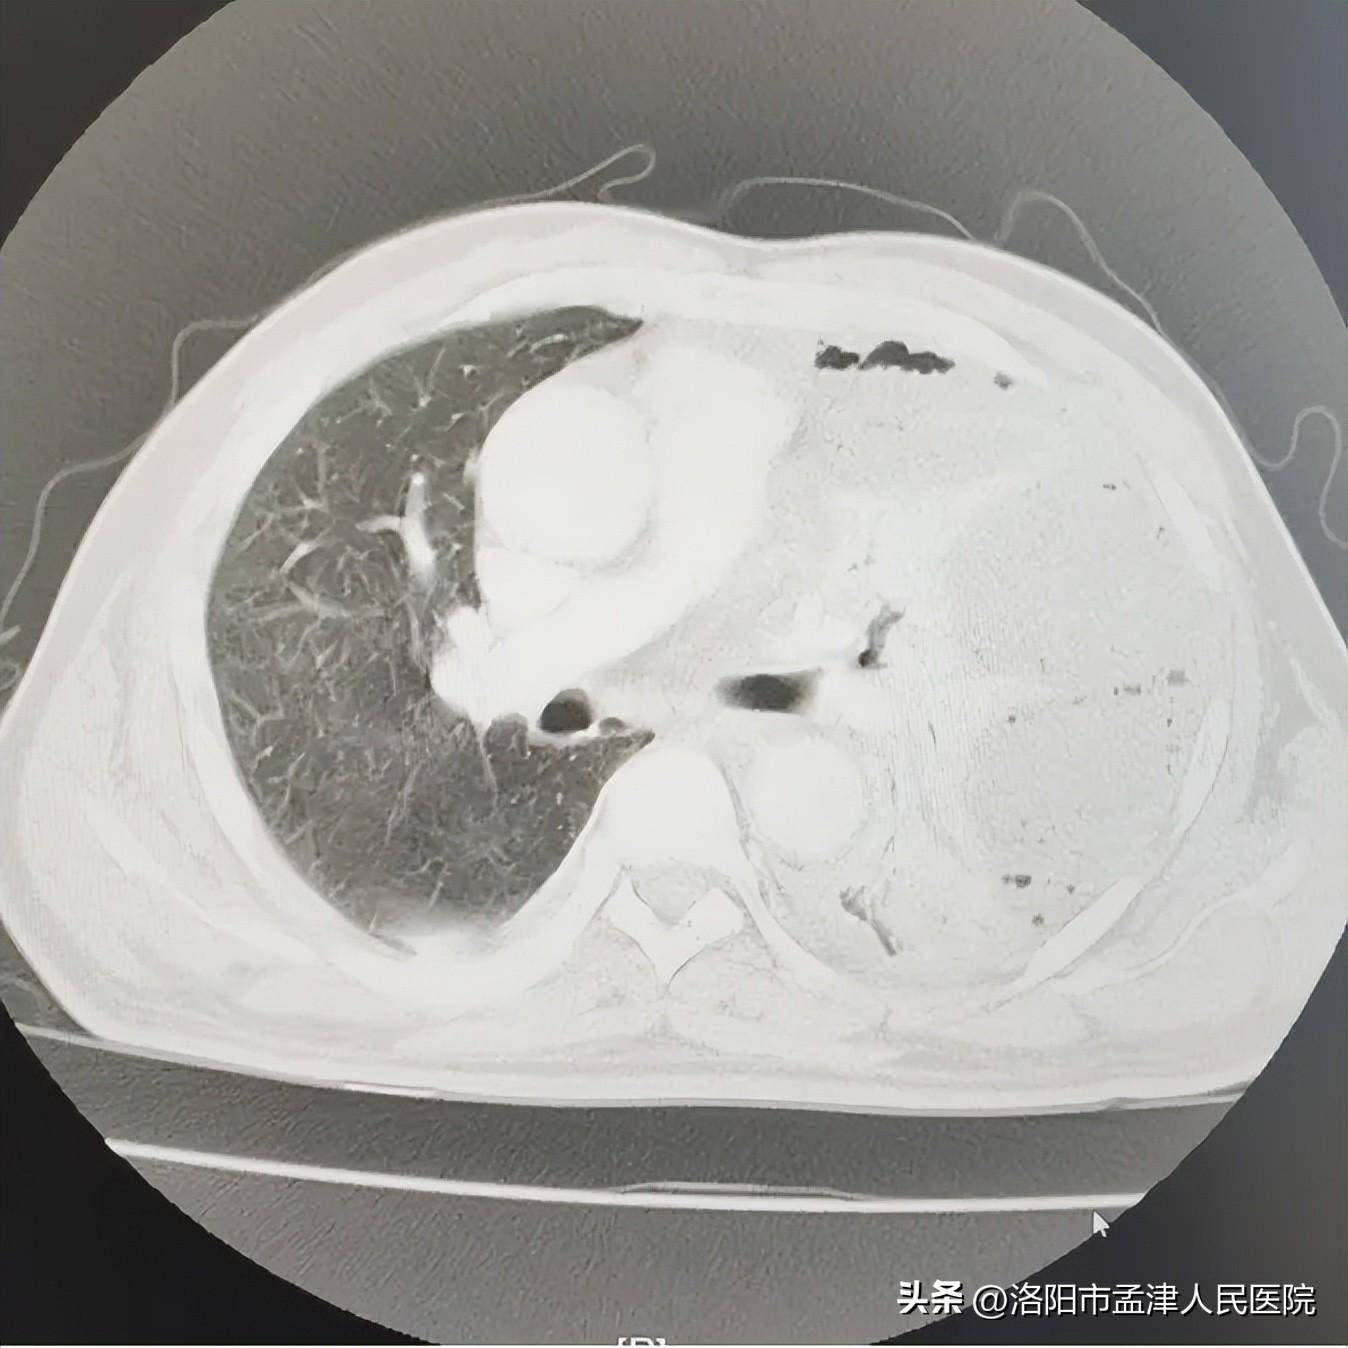

孟津人民医院胸外科为脓胸患者解除病痛

图片尺寸1348x1348